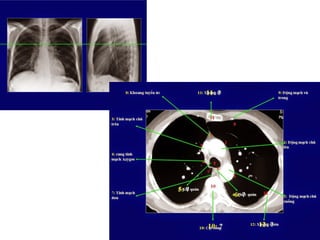

2/XEM HÌNH “SCOUT VIEW” ĐỂ BiẾT VỊ TRÍ LÁT CẮT

PA SCOUT X-RAY

October 31, 2014 6

2/XEM HÌNH “SCOUTVIEW” ĐỂ BiẾT VỊ TRÍ LÁT CẮT PA SCOUT X-RAY October 31, 2014 6